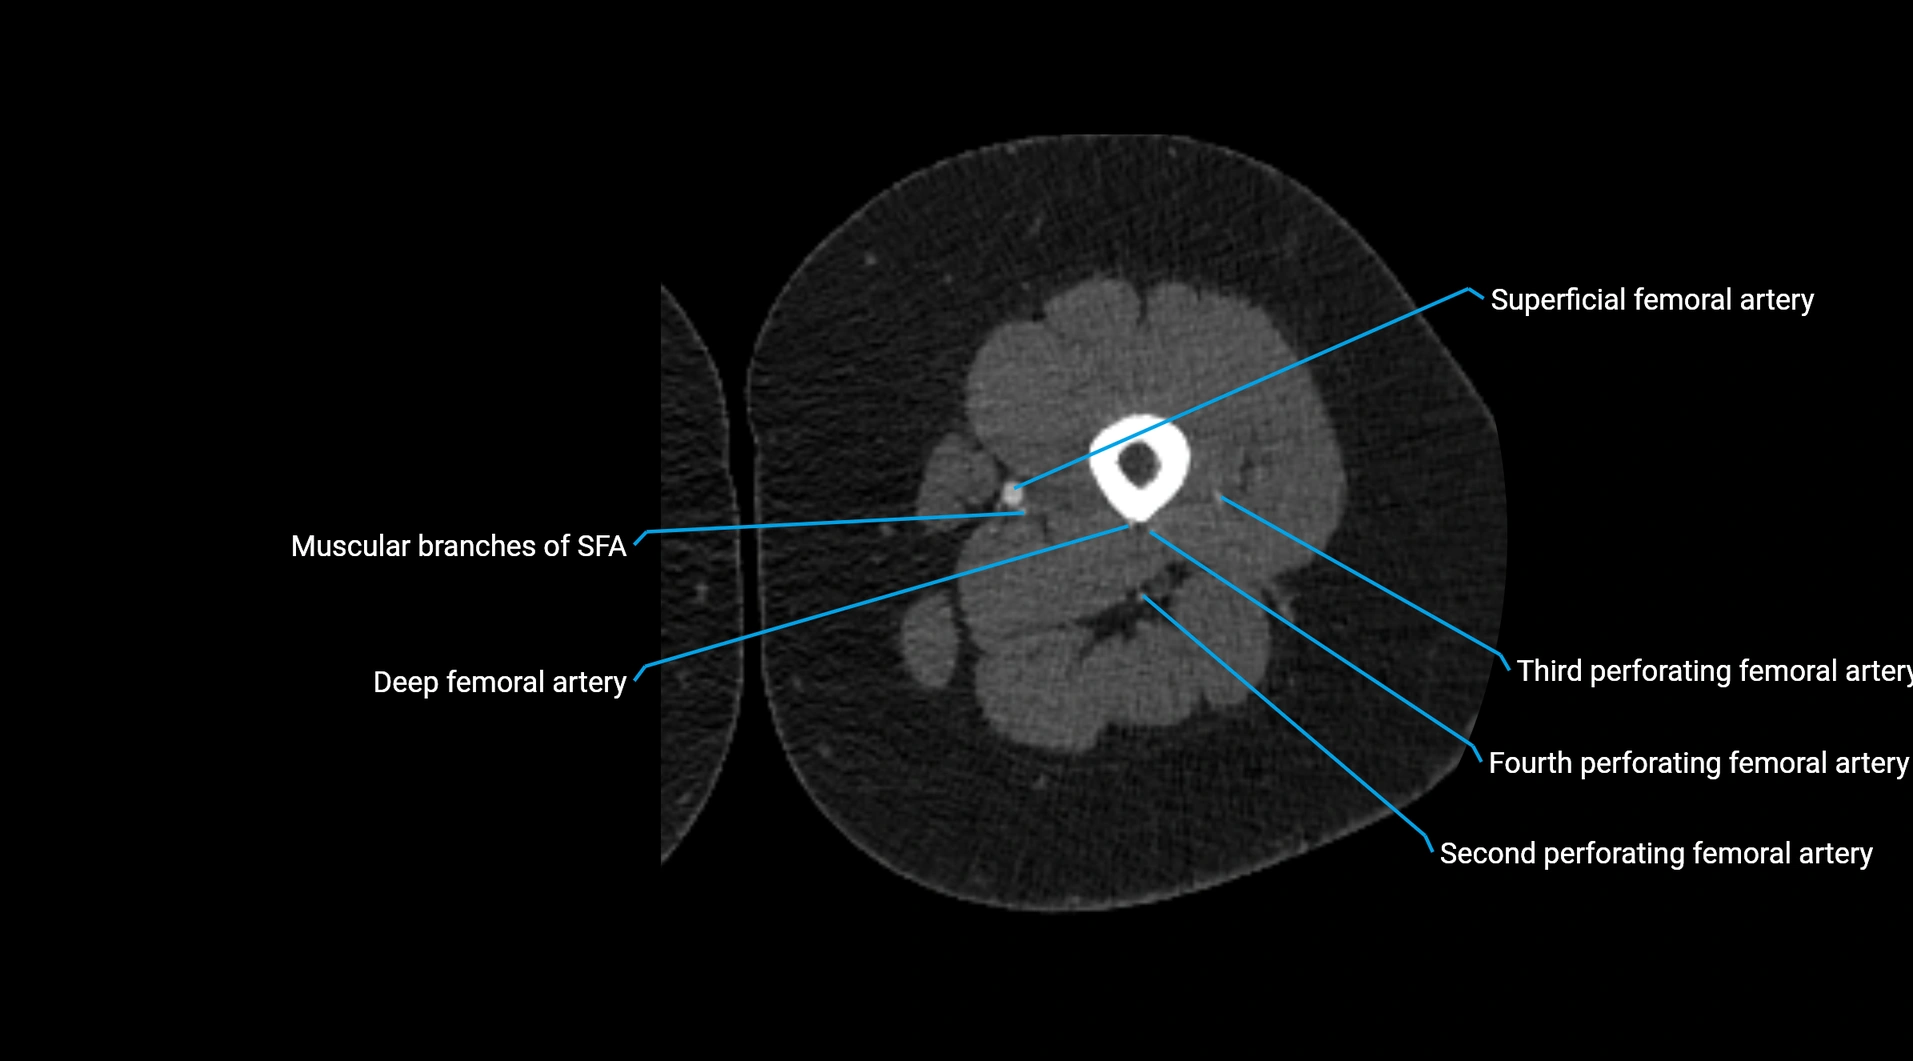

Contrast-enhanced CT (CTA):

• Gold standard for abdominal aortic imaging

• Provides excellent detail of lumen, wall, aneurysm, thrombus, and branch vessels

• Multiplanar and 3D reconstructions help in aneurysm measurement, stent graft planning, and dissection evaluation